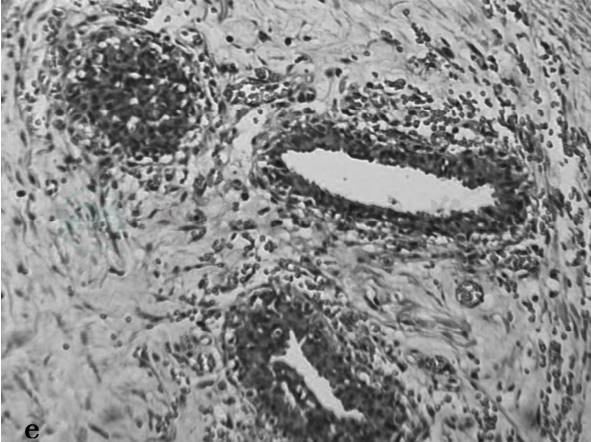

图1 e,病理结果:男性乳腺发育(见文后彩图)

诊断:病例1,男性乳腺发育症